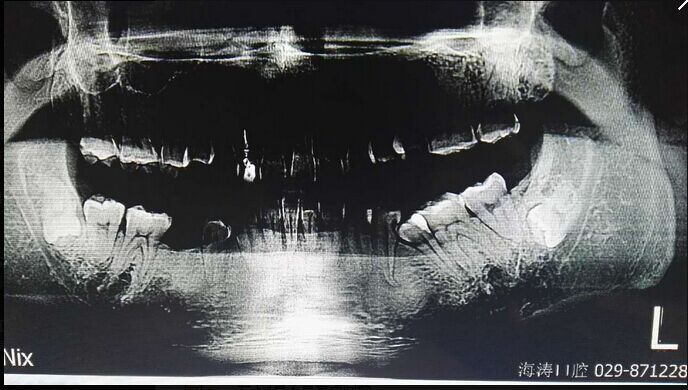

倒置阻生牙拔牙的病案討論

討論四:片子顯示的倒置阻生牙撥牙關(guān)健注意幾點(diǎn),1.翻瓣后去骨部位盡量離7遠(yuǎn)中,別破壞7遠(yuǎn)中骨壁,避免損傷7,以去除8根部的阻力為主。2.暴露阻生牙后,用鉆磨斷部分冠根后,用小骨鑿劈裂冠與根,可避免牙鉆因視野而誤傷神經(jīng)。3.冠根裂開后,先用牙挺挺出根部,然后挺出冠部。

提問(wèn):對(duì)7號(hào)牙沒(méi)有影響的埋伏智齒,是不是可以不拔?

答:一般情況下,完全骨埋伏阻生牙患者如無(wú)不適癥狀不會(huì)要求撥牙的,很多時(shí)候是口腔內(nèi)其它問(wèn)題拍片時(shí)發(fā)現(xiàn),但醫(yī)生發(fā)現(xiàn)這種情況要告知患者將來(lái)可能會(huì)發(fā)生什么問(wèn)題,例如頜骨囊腫,7號(hào)牙松動(dòng)等等,畢竟這個(gè)8號(hào)牙是潛在的病灶牙,究竟撥與不撥得讓患者作主,我們得盡到告知義務(wù)。往往最后決定撥這類牙的患者都是有各種不適癥狀的。

至于對(duì)7號(hào)牙暫時(shí)沒(méi)有影響的埋伏牙,不等于以后永遠(yuǎn)不影響。